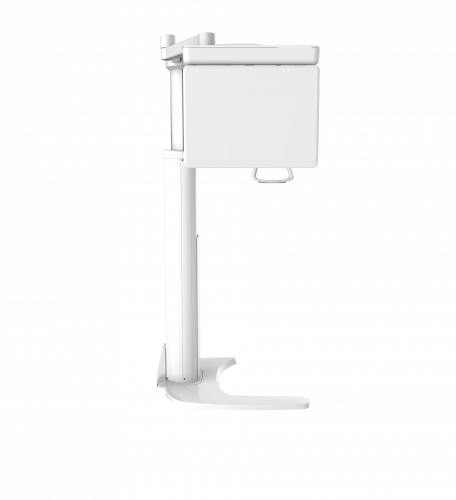

| TYPE | TOP VIEW | FRONT VIEW |

|---|---|---|

|

PaX-i (Pano) |

|

|

|

PaX-i SC (Pano/Scan Ceph) |

|

|